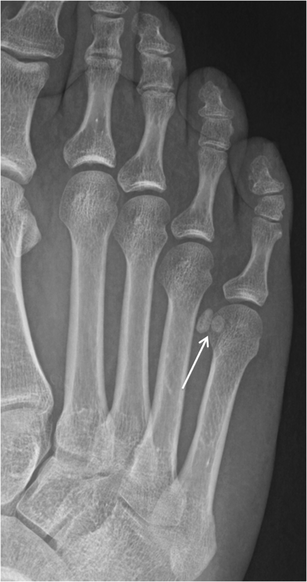

Lesser metatarsal sesamoids

Bipartite lesser metatarsal sesamoid. Bipartite fifth metatarsal sesamoid is shown (arrow), with ell-corticated rounded fragments that do not fit together